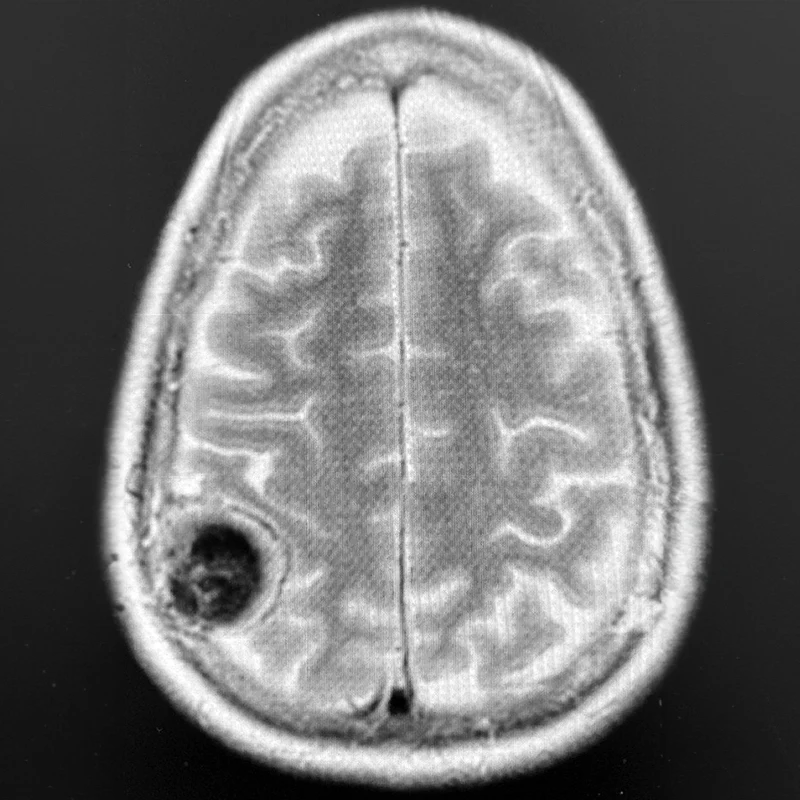

Figure 1. This composite figure illustrates intraoperative mapping of primary somatosensory cortex at high resolution using 2,048 surface microelectrodes.

Top Left. Axial T2-weighted brain MRI showing a 4-cm right parietal meningioma compressing the postcentral gyrus (hand and arm primary somatosensory cortex) in a patient who originally presented with a seizure involving sensory and motor changes on the left side of the body.